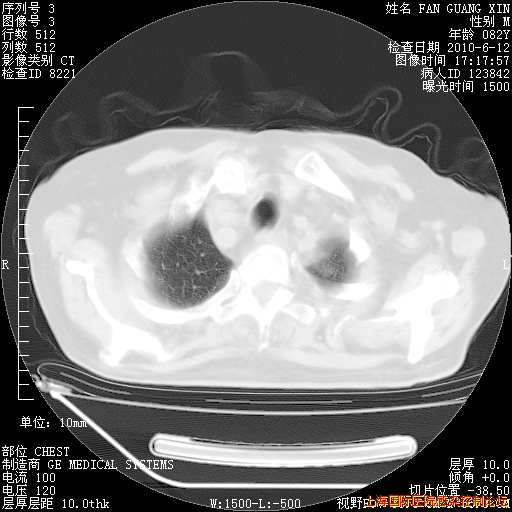

6月12日肺窗

补发6月12日肺部CT肺窗